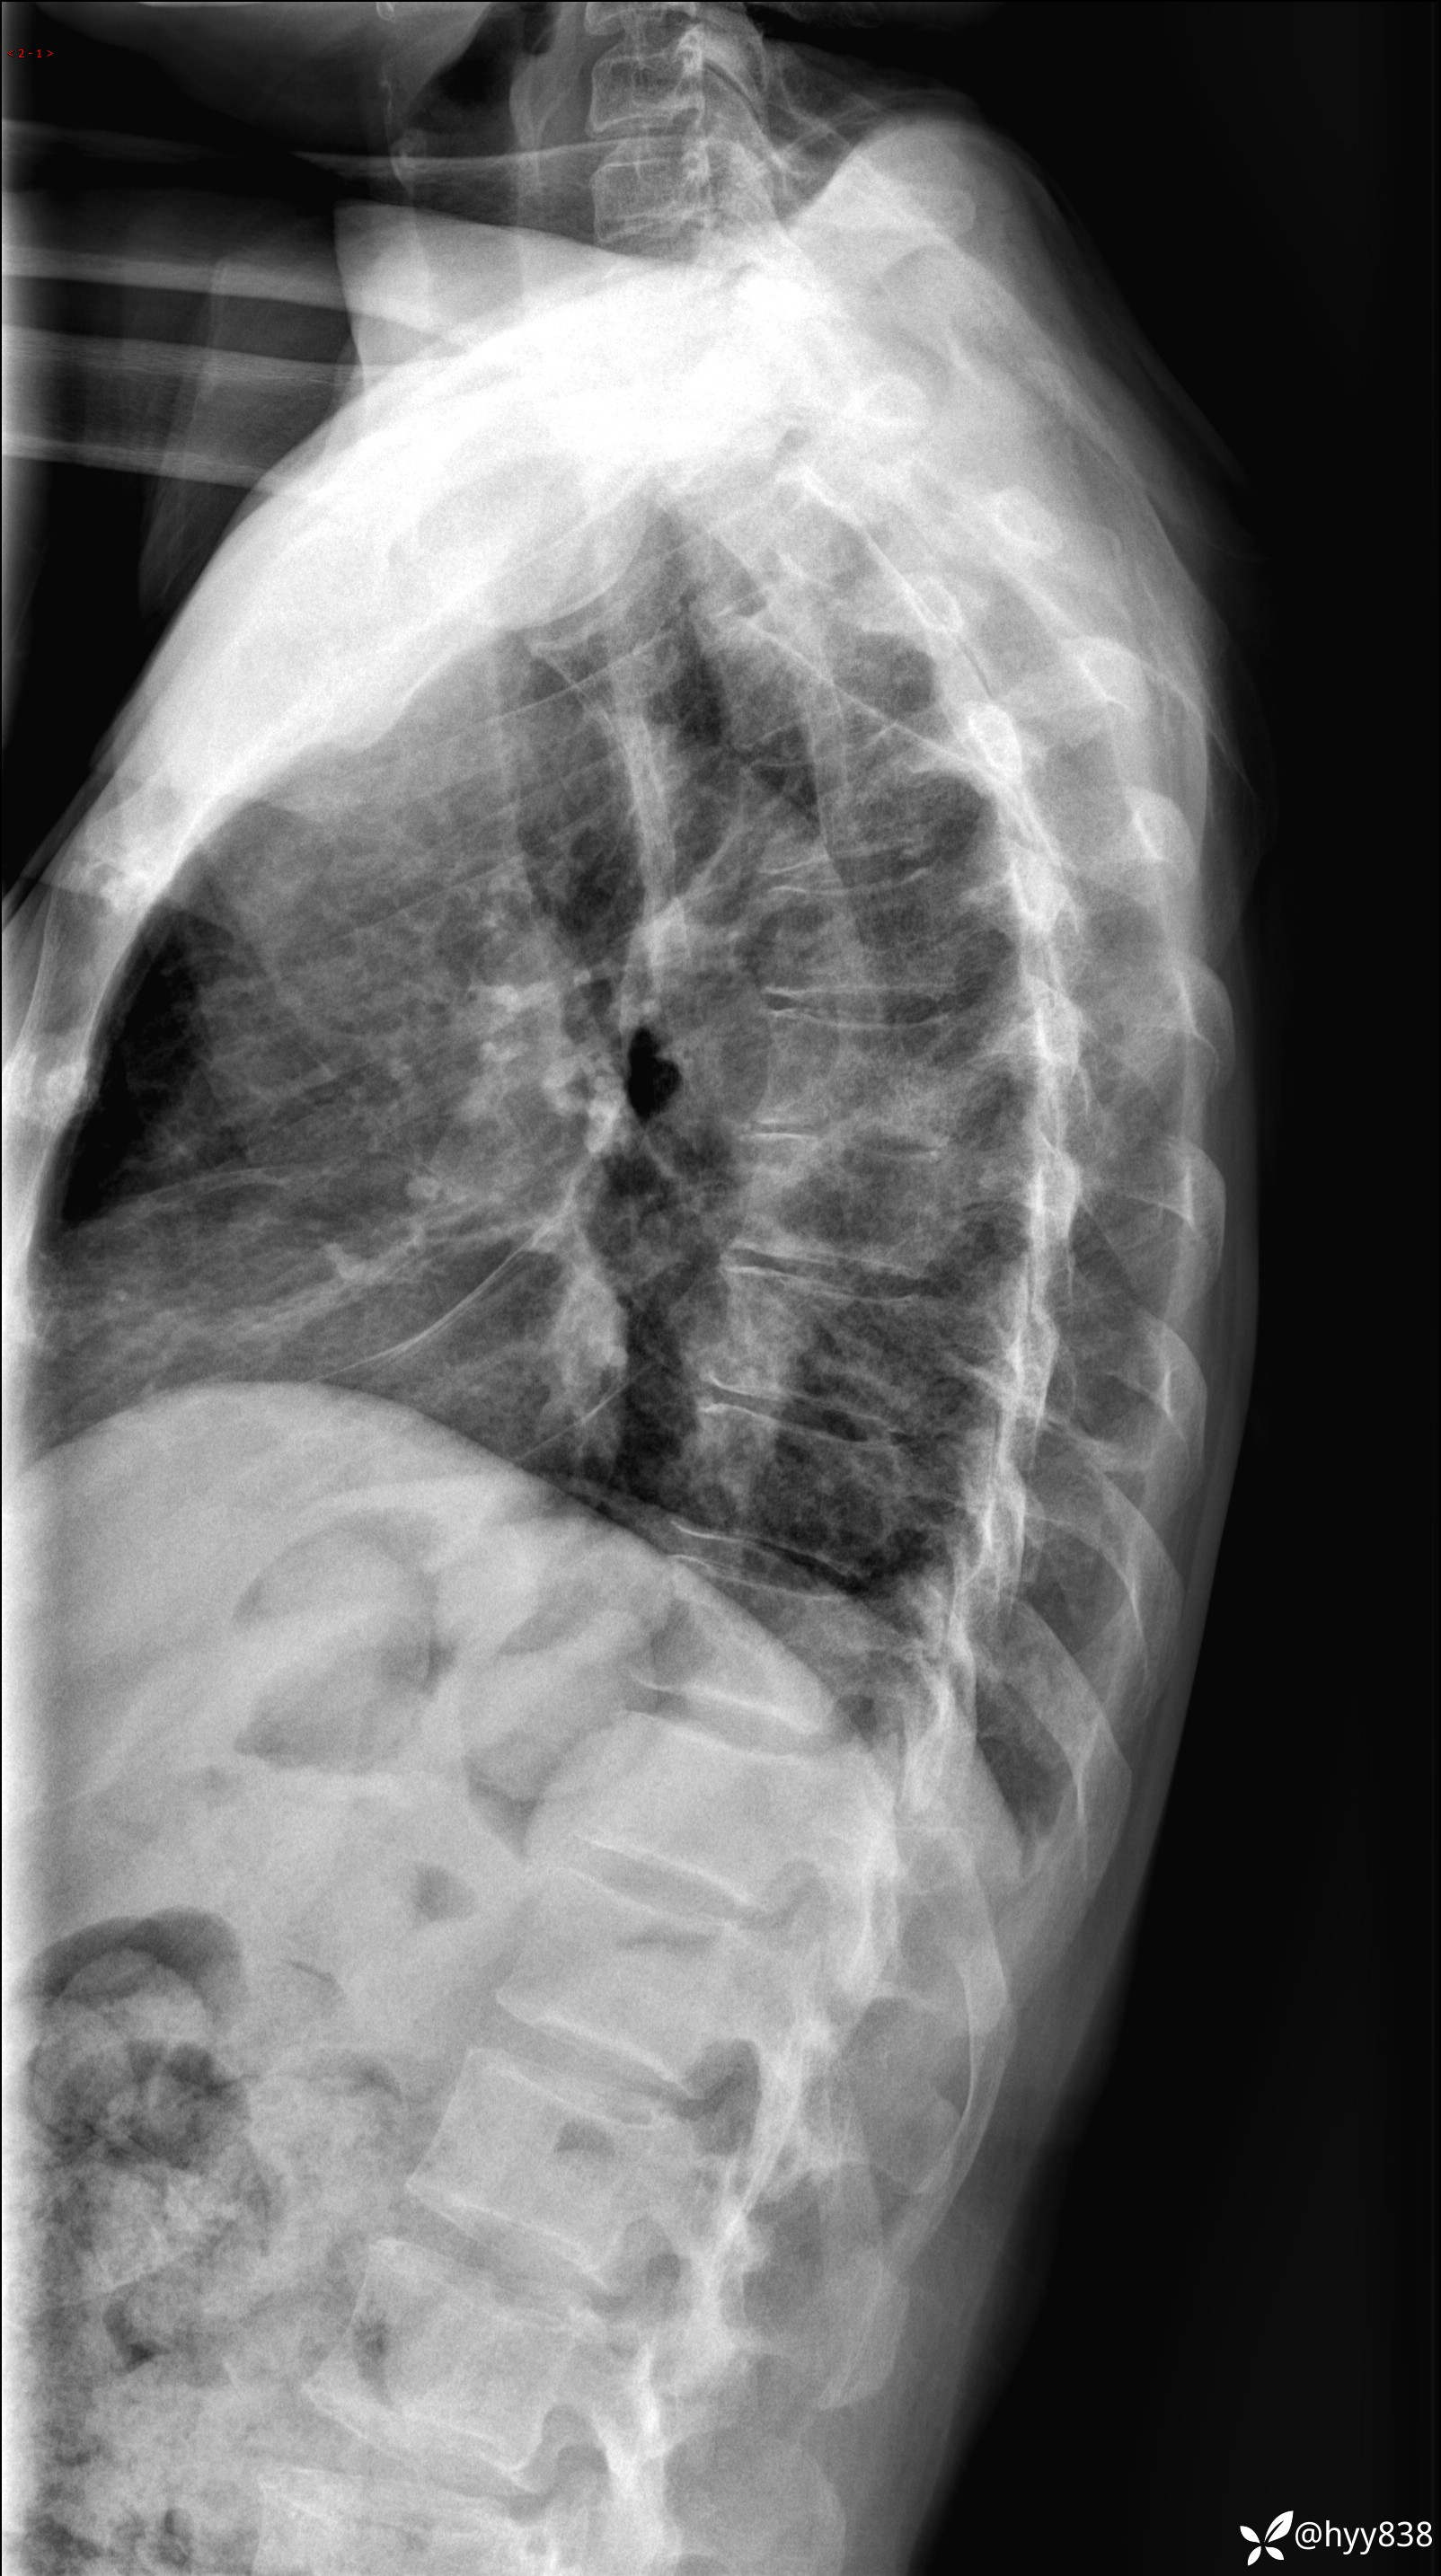

性别:男

年龄:55岁

简要病史:腰背部疼痛伴年余

胸椎正侧位片